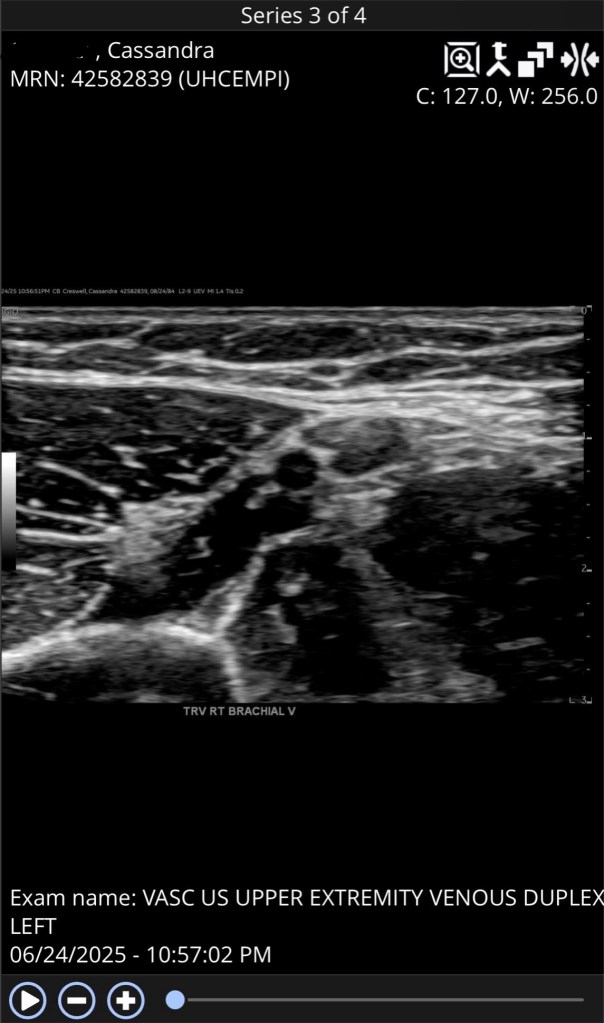

They took my vitals, and immediately took me back. I didn’t even sit down in the waiting room. They put me in kind of a big, private room. Then.. all the tests started. They took some blood first, then sent me for an ultrasound. I was in there for what felt like forever. When I was back in my room, they came in and did a chest X-ray. Then more bloodwork. Then I went for a CT scan. Side note.. contrast is terrible. I legitimately thought I peed my pants right there on the table. They took a urine sample, too. They did an ECG when I got back to my room. After hours of waiting, I finally got all of my test results back. Everything was perfect. Middle of the line, perfect.. minus the dreaded blood clot. They found it during the ultrasound. But the crazy part is, it’s in my arm. Only 3:100,000 DVTs are found in the arm annually. One of my brachial veins won’t compress and there was no sign of blood flow. They have no explanation. I’m a very healthy person. My bloodwork was perfect. My urine was perfect. Heck, they flagged it because it was “too clear”. I haven’t fallen. I haven’t had an IV or surgery. No one is hitting me. There is literally no reason why this should’ve happened. They gave me a prescription of blood thinners and told me to follow up with my doctor. Except.. I don’t have one. Or insurance.